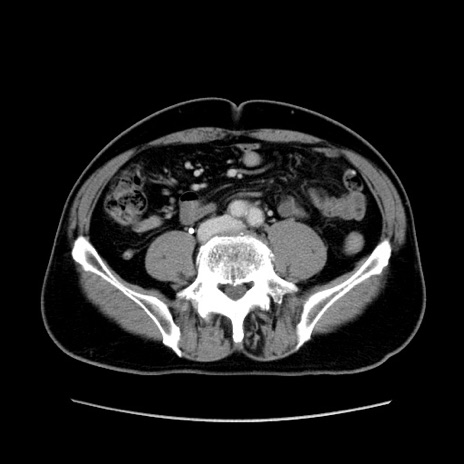

症例34(横断像)

【症例】60歳代 男性

【主訴】右鼠径部膨隆

【現病歴】1年程前より右鼠径部膨隆あり。自己にて還納可能だったため放置していた。3時間前より右鼠径部の脱出を認め、還納困難となり受診。

【身体所見】右鼠径部に小児頭大の膨隆あり。弾性硬であり、用手還納は困難。左鼠径部にも膨隆を認める。脱出はなし。